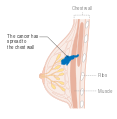

| رسم لسرطان الثدي. | |

المرحلة الرابعة أو النقيلية من سرطان الثدي.